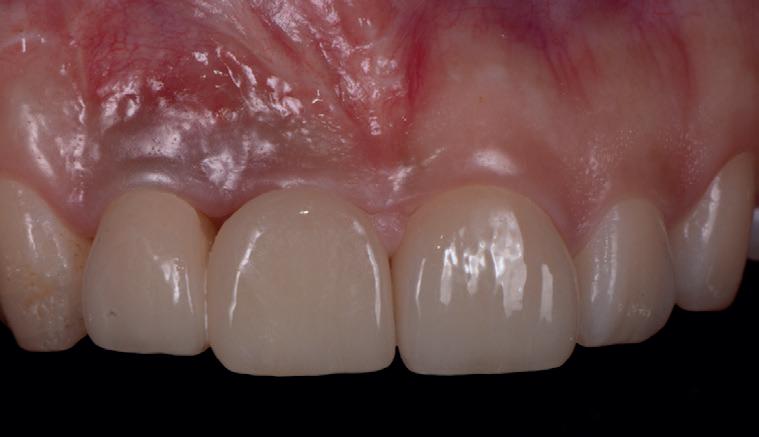

SITE AUGMENTATION Reconstituirea țesutului moale periimplantar și papilar în zona estetică

RECONSTITUIREA țesuturilor moi periimplantare. Scopul acestui raport de caz este de a demonstra procedurile chirurgicale utilizate pentru corectarea unui defect al țesuturilor moi periimplantare folosind țesutul moale interdentar în combinație cu tuberozitatea ca locație donatoare de țesut conjunctiv, utilizând o abordare prin tunelizare într-o zonă estetică.